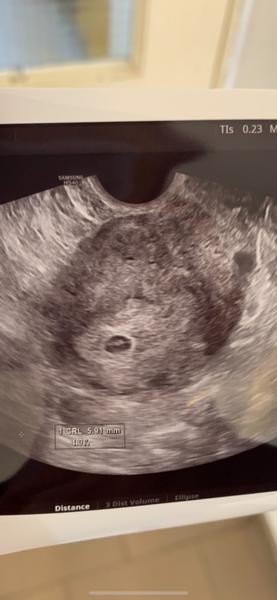

Byla jsem dneska u mudr ,na utz zatim nebylo nic videt ,vzala mi krev a pri prohlídce rikala ,ze nikde neshledala nejaky problem a spineni je normalni ,ze se muze objevit v termínu kdy mela prijit ms. Tak uvidime co bude dal